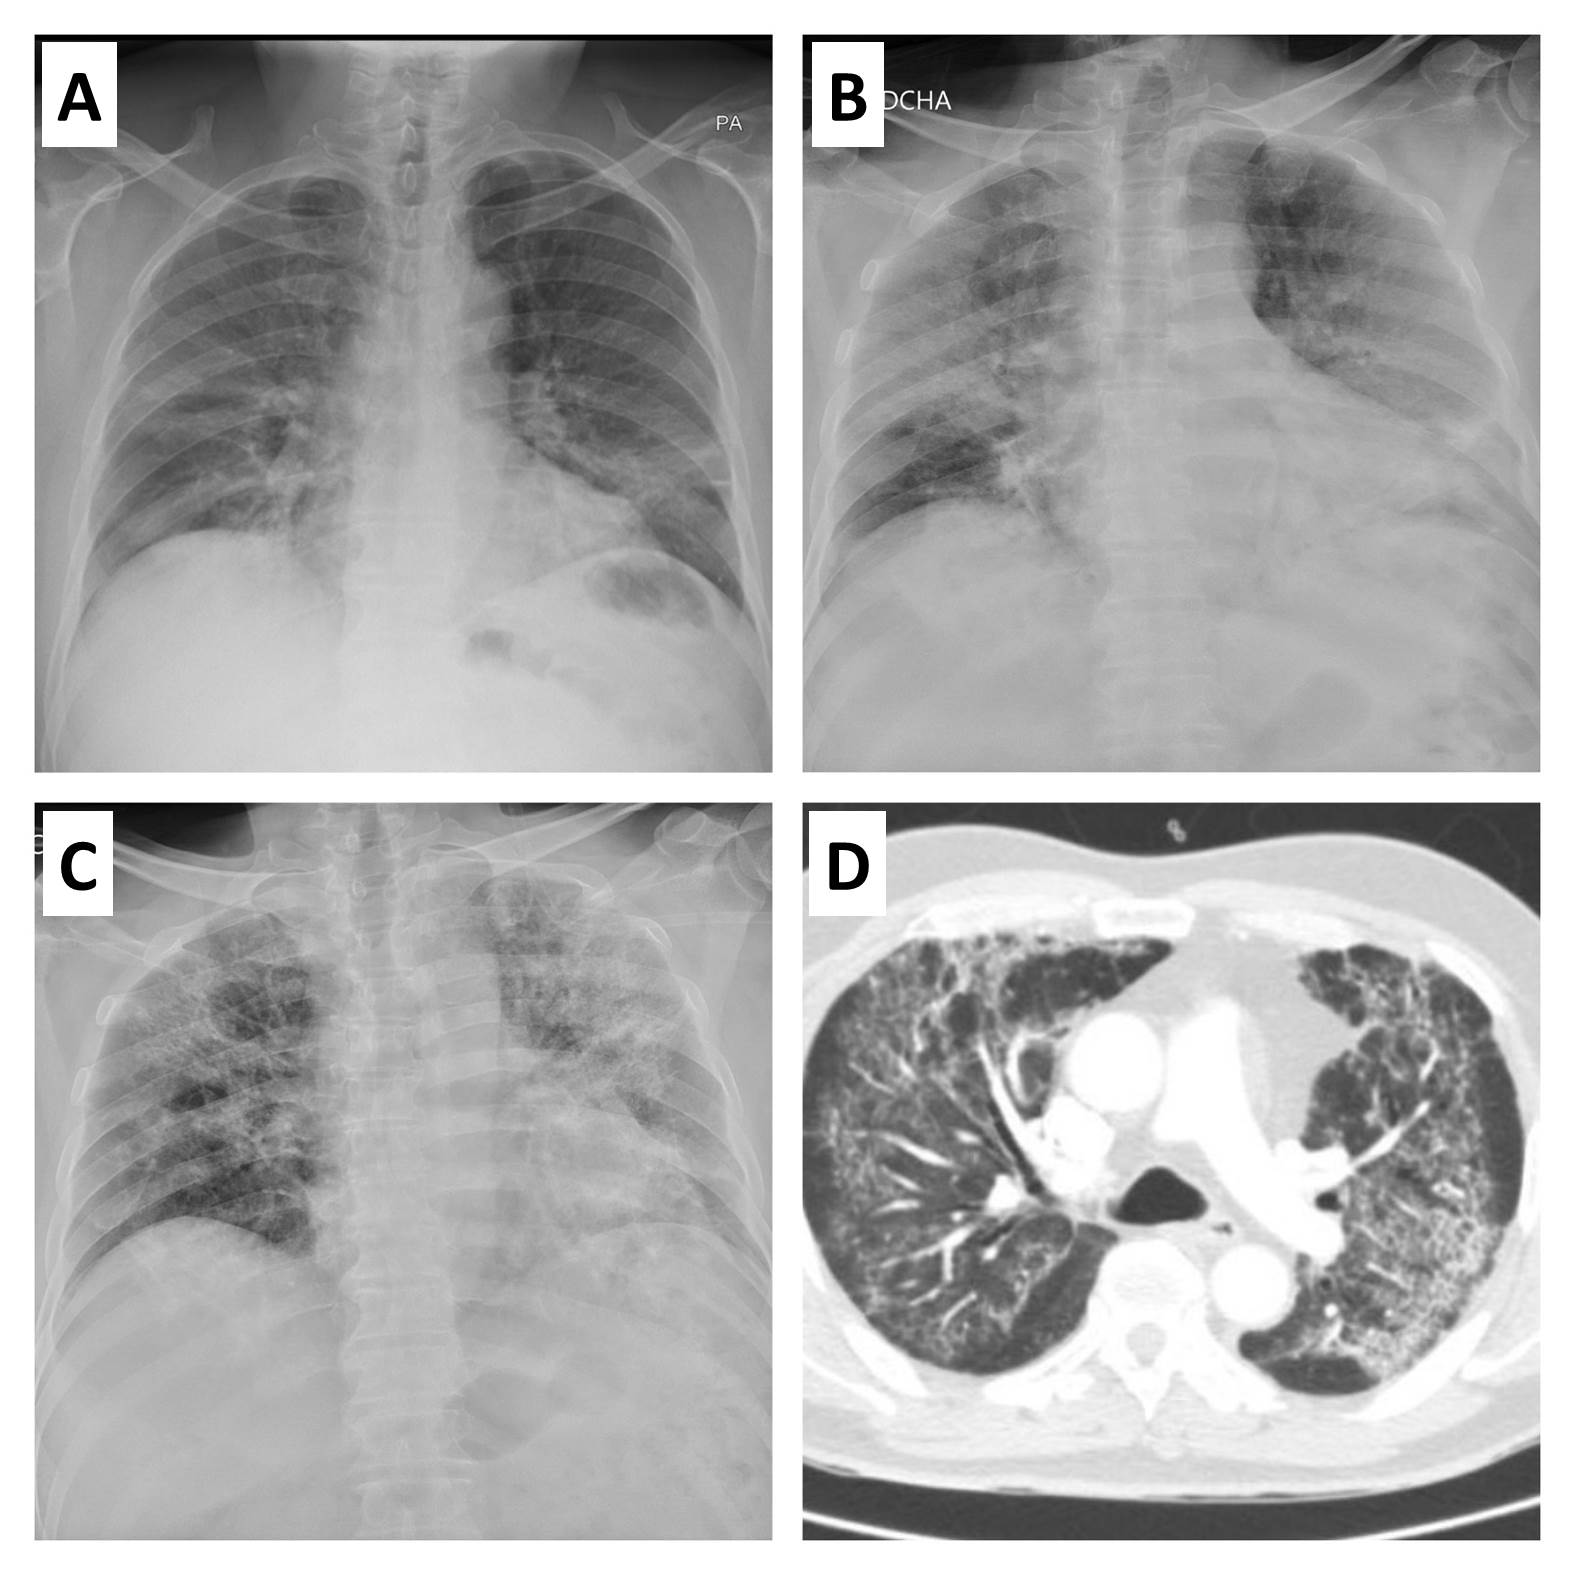

Durante el mes de diciembre de 2019 se comunicaron en Wuhan, la capital de la provincia de Hubei, China, los primeros casos de neumonía asociada a la nueva variante de coronavirus 2 del síndrome respiratorio agudo grave (SARS-CoV-2)?. Durante el primer trimestre de 2020, la enfermedad por coronavirus de 2019 (COVID-19) experimentó una rápida expansión global, poniendo a prueba los sistemas sanitarios y financieros de las principales potencias del mundo. Paralelamente, el extraordinario esfuerzo en investigación ha permitido ampliar el conocimiento de la enfermedad, y en concreto de la afectación de otros órganos y sistemas más allá del aparato respiratorio. En la presente revisión se enumeran los aspectos clínicos más importantes en el manejo de los pacientes con COVID-19 desde el punto de vista cardiológico, desde la afectación miocárdica, al manejo de procesos cardiológicos específicos.